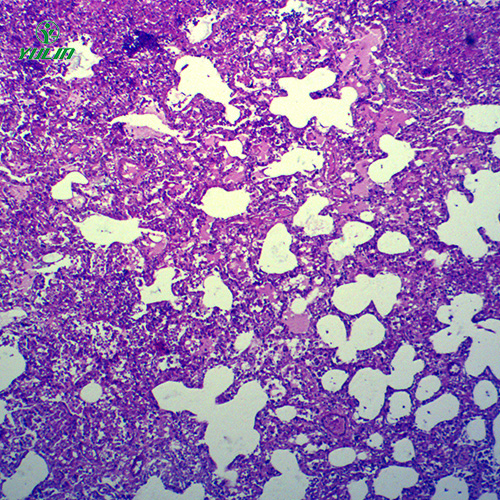

动物切片的制作需结合动物组织的特性进行优化。针对不同类型的动物组织,采用适配的处理工艺,如肌肉组织(纤维结构密集)需在切片前进行充分的软化处理,确保切片均匀;神经组织(结构脆弱)需采用更精细的切片工具,避免切片过程中出现结构破损。染色环节会根据组织特点选择染料,如观察细胞核与细胞质的关系常用苏木精 - 伊红染色法(细胞核呈蓝色,细胞质呈粉红色),观察脂肪组织常用苏丹染液(脂肪颗粒呈橘红色),通过染色清晰区分不同细胞结构与组织成分。同时,动物切片的保存需注意环境温度与湿度,避免高温、高湿环境导致切片变质或染色褪色。

使用动物切片开展教学时,可结合教学目标设计观察任务。例如在讲解动物组织类型时,让学生通过观察肌肉组织切片(区分骨骼肌、平滑肌、心肌的纤维形态差异)、上皮组织切片(观察上皮细胞的排列方式),理解不同组织的结构与功能适配性;在讲解器官结构时,让学生通过观察肝脏切片(识别肝细胞、肝血窦的结构)、肾脏切片(观察肾小球、肾小管的形态),了解器官的微观组成与生理功能。观察过程中引导学生做好观察记录,绘制切片中的细胞或组织形态,加深对动物微观结构的理解与记忆。使用后的动物切片按照规范进行清洁与保存,确保切片可重复使用,为后续教学提供持续支持,助力动物学教学的实践开展。